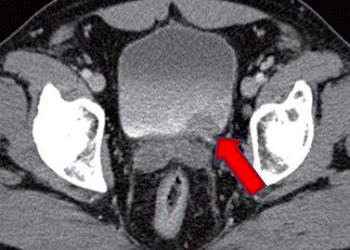

Mesane kanseri tanı ve tedavisi